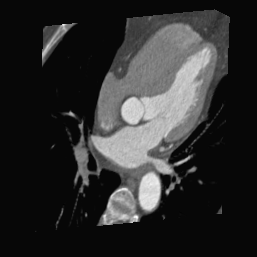

4.3.2 Effect of Different Network Architectures

As shown in Table 4, we assess the effect of five different network architectures on PosNet for each registration method. It can be seen that the transformer-based Swin-T outperforms all CNN-based backbones, with 0.35∘ and 0.37mm smaller rotation and translation errors than the best CNN-based ResNet18 in the SyN registration. This may be because global information is crucial for locating 2D slices within 3D space. Moreover, the self-attention mechanism with shifted windows in Swin-T can efficiently capture global and local information, and its hierarchical design facilitates multi-scale feature extraction. As a result, it exhibits a stronger feature representation capability, achieving superior performance. In addition, among the CNN-based backbones, ResNet18 achieves the lowest rotation error and translation error in all registration methods. Specifically, in the SyN registration, the mean rotation and translation errors of ResNet18 are smaller than those of ResNet50, MobileNetV2, and VGGNet19 by 0.03∘, 1.23∘, 1.76∘ and 0.02 mm, 0.50 mm, 0.36mm. We can observe that the errors of ResNet18 and ResNet50 are similar, with ResNet18 performing slightly better but within the error margin. This indicates that simply increasing the number of layers does not reduce the error, whereas switching to the transformer-based architecture resulted in lower errors. This further emphasizes the importance of global information for locating 2D slices in 3D space. Fig. 7 presents examples of predictions made by the optimal PosNet. The first row is the given six query images, and the second row is 2D slices resampled from the SyN atlas volume using the positions predicted by PosNet. From the slices shown in all columns, PosNet can distinguish critical anatomical structures and perform precise slice positioning.

(a) 2C

(b) 4C

(c) Y

(d) RV1

(e) RV2

(f) RV3